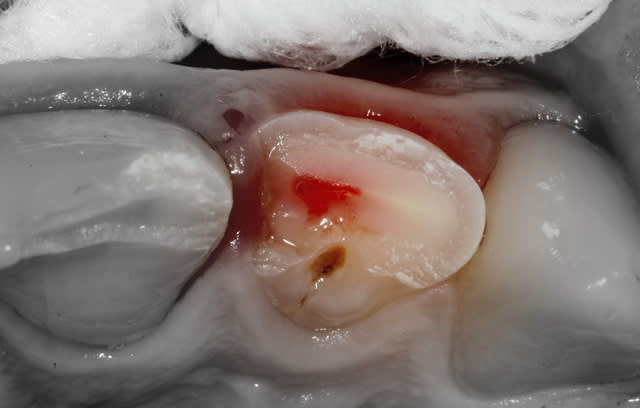

- 22 présente une exposition pulpaire ancienne de 20 heures. 20 heures donc que les germes buccaux contaminent directement la pulpe, heureusement jeune et donc avec un fort potentiel de défense.

Une pulpotomie partielle est réalisée afin d'éliminer le tissu le plus contaminé. De la Biodentine est utilisée ; son avantage par rapport au MTA est de ne pas noircir. Du CaOH aurait un taux de succès moindre.

Sur la photo4, celle apres la pulpo partielle je suppose, as tu eu une hémostase naturelle ? As tu directement posé le MTA ? La pulpe semble assez "rouge foncé"

- L'hémostase est faite avec un coton stérile (des boulettes de coton dans un sachet passé à l'autoclave).